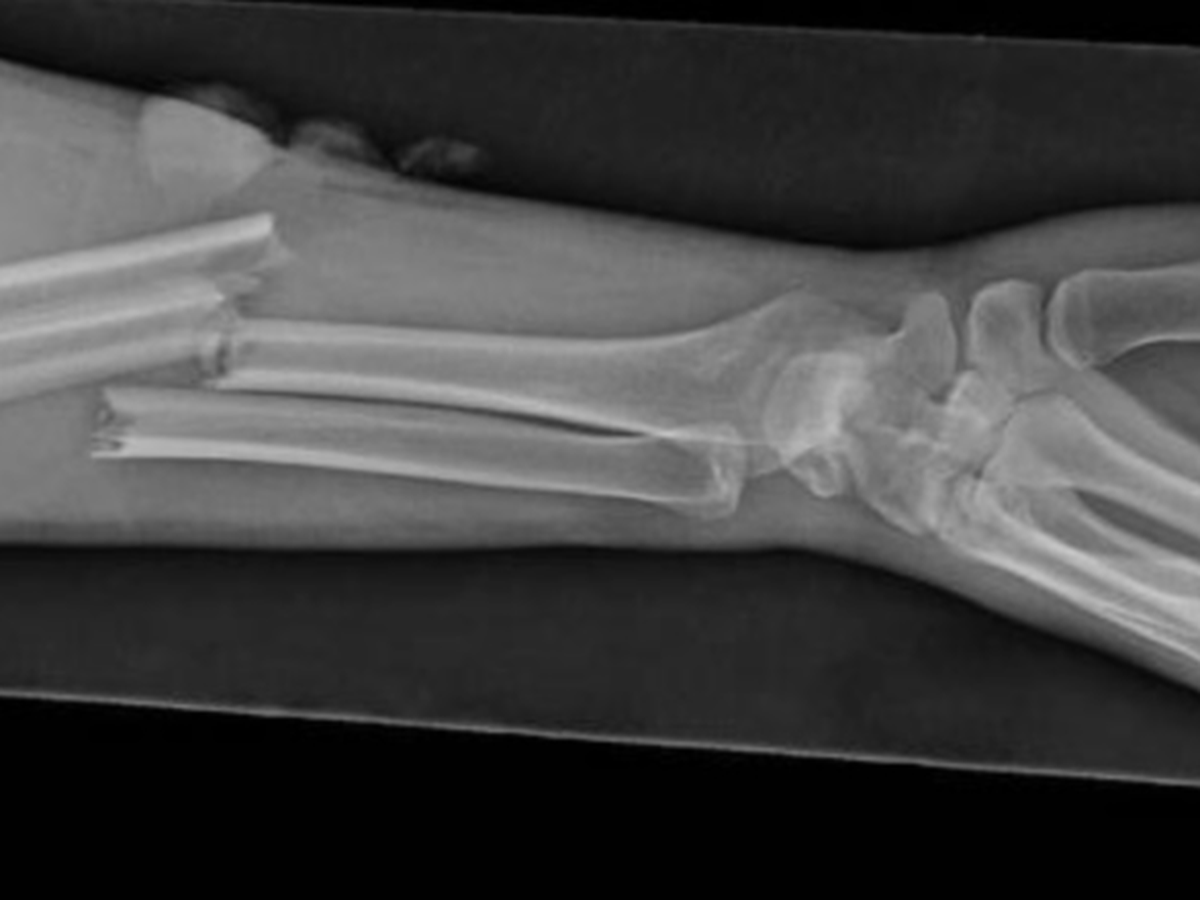

Hi everyone. I wanted to reach out and see if anyone might be able to help this gentleman who lives in Zarqa, Jordan. (I will keep his name anonymous for privacy purposes; but I can vouch that I personally know him). His 10 year old son fell and shattered his arm. He took him to the community (free) hospital (مستشفة الحقومه) and they told him that his son’s surgery would be out of their scope and that he needed to take him to a more advanced facility for surgery. So he took him to a “private” hospital in Jordan that demanded a certain amount of money before performing surgery. (In places like Jordan, in private hospitals you have to pay BEFORE your care) So naturally, seeing his son in the shape that he was in, he begged the hospital to perform the surgery under the promise that he would pay them back by weeks end. Which leads me to this Gofundme. I know many of you have been so generous this past year in particular. We are so incredibly blessed in so many ways. I reach out to my tribe to see if we can continue to help others in need. I’m trying to raise 1500 in the next few days in order to cover the boys surgical costs. The father whatsapped me in the middle of the night saying he was in the mosque praying that God would help them in their time of need. Please help me help them make their prayers become a reality. Thank you for your kindness, love and generosity in advance